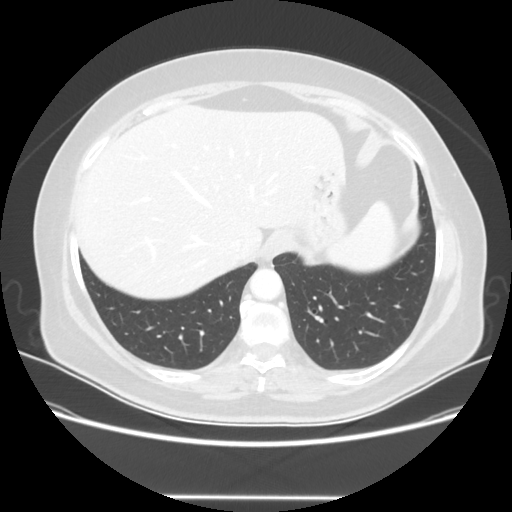

Generated VENOUS CT scan (A→B translation)

No window - Raw intensity values

Lung window (WL -600, WW 1500 β†’ Low βˆ’1350, High +150)

Targeted Slice 70 - Lung Window Analysis (Generated vs Real Venous)

0.782

Lung SSIM

70.6

Lung RMSE

32.3

Lung MAE

Average Lung Window Metrics Across All Slices (25 slices) - Generated vs Real Venous

0.771

Lung SSIM (Avg)

72.3

Lung RMSE (Avg)

34.1

Lung MAE (Avg)